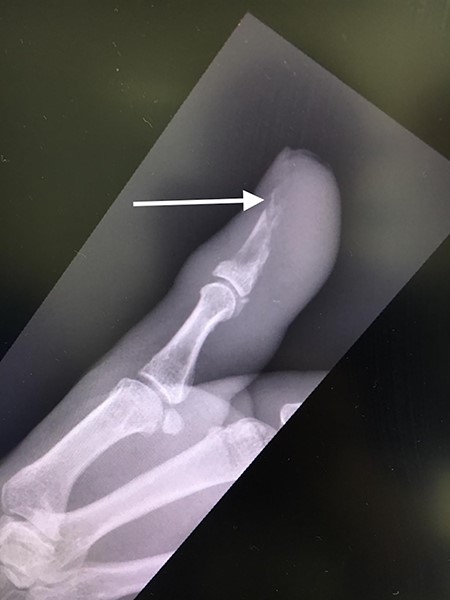

The patient was then reviewed 6 weeks after her initial presentation, following the results of the sarcoma MDT, which confirmed a benign tumour. At this point, the patient reported some tenderness around the surgical incision, but that her symptoms were improving. It was thought that she had no signs of ongoing infection in the thumb. The outcome was for monitoring of her symptoms with no indication for surgical excision. She had a follow-up X-ray in 6 weeks’ time that showed resolution of the lytic lesion (Figs 6 and 7).

Lateral follow-up radiograph of right thumb 6 weeks post-admission showing resolution of lytic lesion.